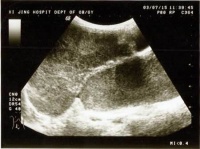

(一)B超:可明确肿瘤的大小形态囊实性部位及与周围脏器的关系鉴别巨大卵巢囊肿及腹水